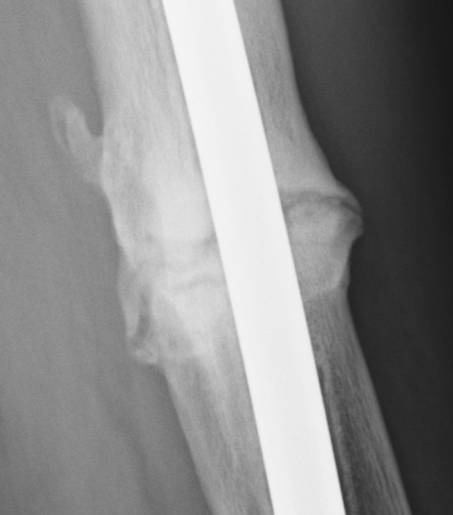

June 22, 2010 X-ray update

Forive me people for I have sinned. It has been two years since my last update. But seriously, there is much improvement to report. Based on activity and how it feels things are progressing very well. The x-rays also show more bone growth which adds to the good sign.

Feb. 21, 2008 June 22, 2010